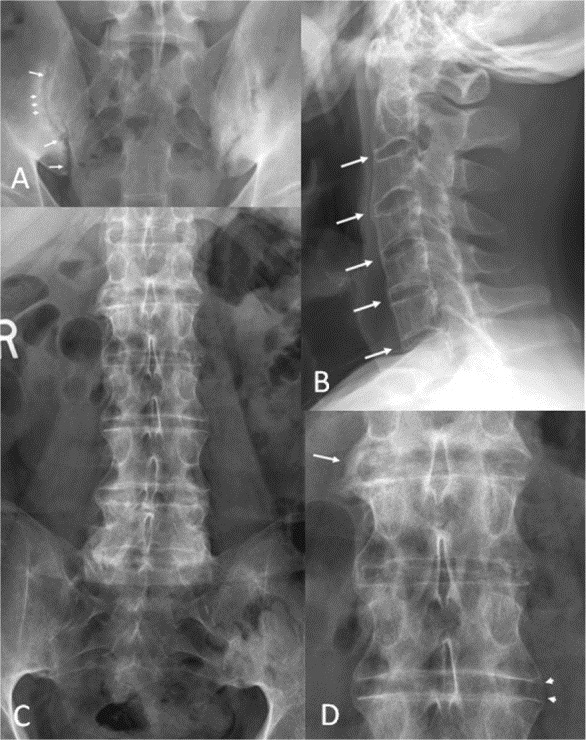

Рентгеновские лучи — важный инструмент для подтверждения диагноза. Исследование позволяет на ранних стадиях заболевания выявить изменения в крестцово-подвздошном сочленении. На рентгеновских снимках можно заметить признаки двустороннего сакроилеита. Выделяют следующие стадии на изображениях:

- На первой стадии наблюдается размытость контуров сочленения, суставная щель начинает расширяться.

- На втором этапе рентген показывает сужение суставной щели, выраженные признаки склероза хрящевой ткани и единичные эрозии.

- На третьей стадии рентген выявляет начало частичного анкилоза в сочленении.

- На четвертой стадии фиксируется полное развитие анкилоза.

Для полноценной диагностики также необходимо исследовать периферические суставы. Это включает рентгенографию для выявления остеофитов, остеосклероза, анкилоза других суставов и эрозивного артрита в мелких суставах стоп. Однако рентгеновские лучи не всегда показывают изменения на ранних стадиях заболевания. В таких случаях целесообразно применять магнитно-резонансную томографию для исследования крестцово-подвздошных сочленений и тазобедренных суставов.